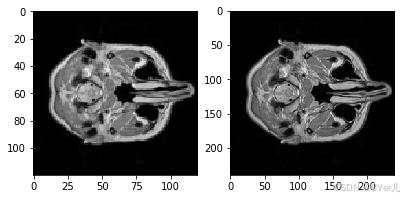

In [8]

# 查看MRI图像

import matplotlib.pyplot as plt

aa = train_LR_data[0,:,:]

bb = train_HR_data[0,:,:]

# 归一化

aa = (aa-aa.min())/(aa.max()-aa.min())

bb = (bb-bb.min())/(bb.max()-bb.min())

fig = plt.figure(figsize=(10,10))

plt.subplot(2,3,1)

plt.imshow(aa,cmap='gray')

plt.subplot(2,3,2)

plt.imshow(bb,cmap='gray')

print(aa.min(),aa.max())

print(aa.min(),bb.max())

plt.show()0.0 1.0 0.0 1.0

<Figure size 720x720 with 2 Axes>